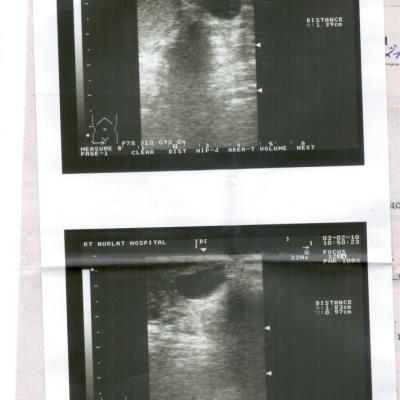

Посмотрите пожалуйста анализы УЗИ

Похоже, что у Вас - осумкованная гематома мошонки, возможно - в области придатка. Сделайте спермограмму, чтобы узнать Вашу фертильность( способность к оплодотворению). Обратитесь к урологу.